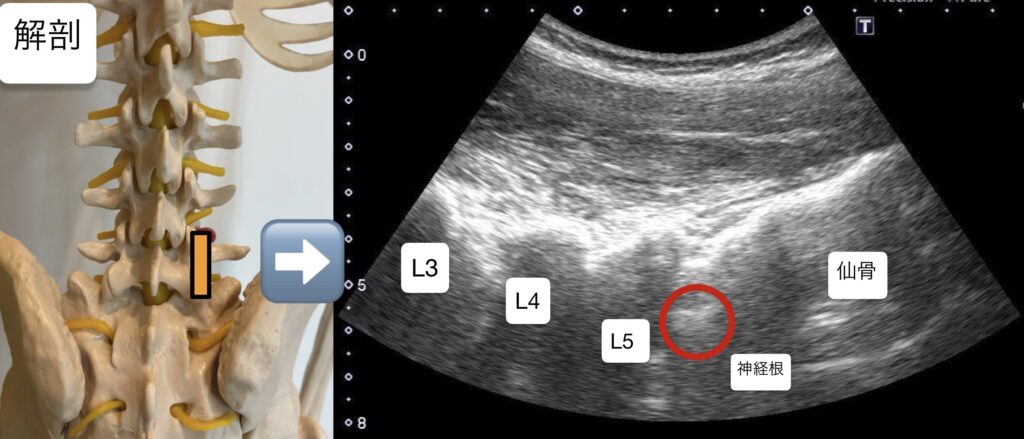

・腰椎5番領域である長母趾屈筋の筋力テストを行ったところ、患側の筋力低下あり。また知覚検査を行ったところL5の皮膚領域において知覚鈍麻あり。

・上記の所見から、腰椎5番の神経根が原因ではないかと考えた。

・腰椎5番神経根に対し、超音波エコーガイド下で鍼通電を行った。